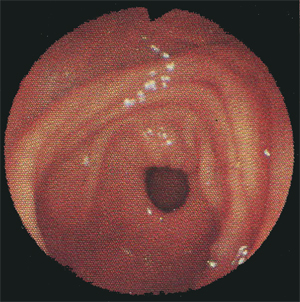

Эндоскопия двенадцатиперстной кишки

На фото хорошо видны круговые складки слизистой оболочки, характерные для двенадцатиперстной кишки